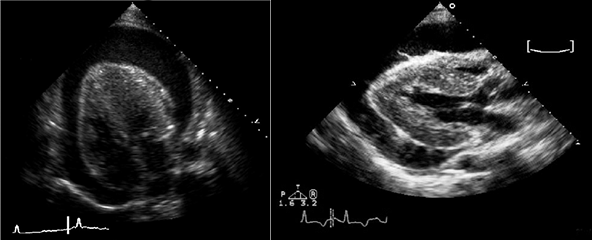

• Эхокардиография: выпот, утолщение перикарда.

• Выпот (>15–35 мл), сепарация эпикарда и перикарда >1 мм в диастолу.

• Величина выпота: малый (сепарация • Утолщение (>3–4 мм) и кальцификация перикарда (констриктивный перикардит).

• Эхокардиография: колебания сердца, выраженный выпот (>20 мм), диастолический коллапс камер сердца, аномальное движение МЖП, > вариабельности митрального потока (>25%) на вдохе.

УЗИ сердца при перикардитах

УЗИ при перикардите